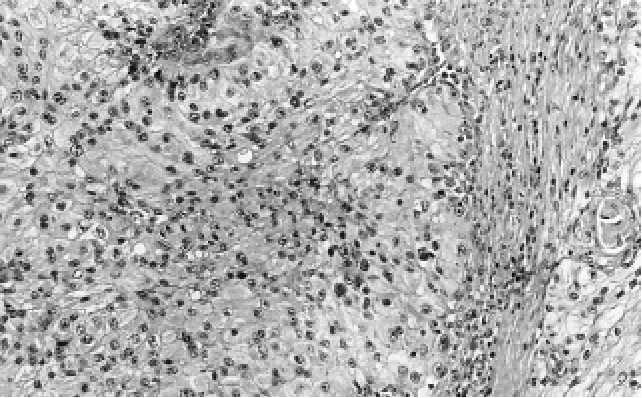

v granulární části a pouze vzácně ve světlobuněčné části tumoru. Sklovité hyalinní

globule byly eozinofilní, sklovitého vzhledu, 1-30 mm v průměru, nacházely se buď-

to intracelulárně nebo extracelulárně. V těch případech, kdy ležely extracelulárně,

měly globule tendenci se shlukovat do houfců (Obr. B.2.7.). Histochemicky byly glo-

Obr. B.2.7. A. Sklovité hyalinní globule byly eozinofilní, sklovitého vzhledu, 1-30 mm v prů-

měru, nacházely se buďto intracelulárně nebo extracelulárně. V těch případech, kdy ležely

extracelulárně, měly globule tendenci se shlukovat do houfců.